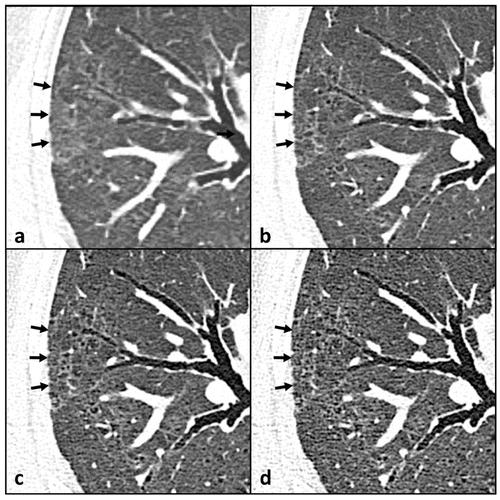

A new computed tomography study reveals that people who smoke marijuana may have a 70 percent higher risk of developing emphysema than non-smokers, and an age-matched subgroup analysis suggests marijuana use could be associated with a 26 percent higher risk of emphysema in comparison to tobacco-only smoking.